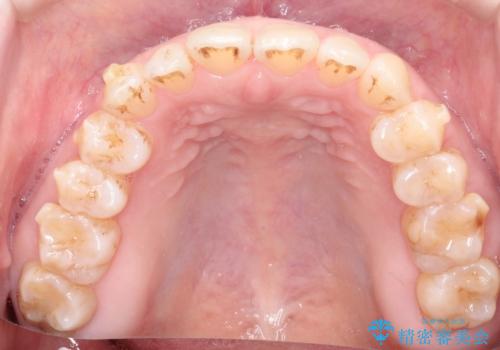

前歯の隙間 インビザラインによる目立たない成人矯正

- 前歯の隙間を気にされて来院されました。

インビザラインにて、目立たずに矯正治療を行うこととしました。

歯と歯の間にある隙間を閉じるのは、インビザラインでもしっかり治療できます。